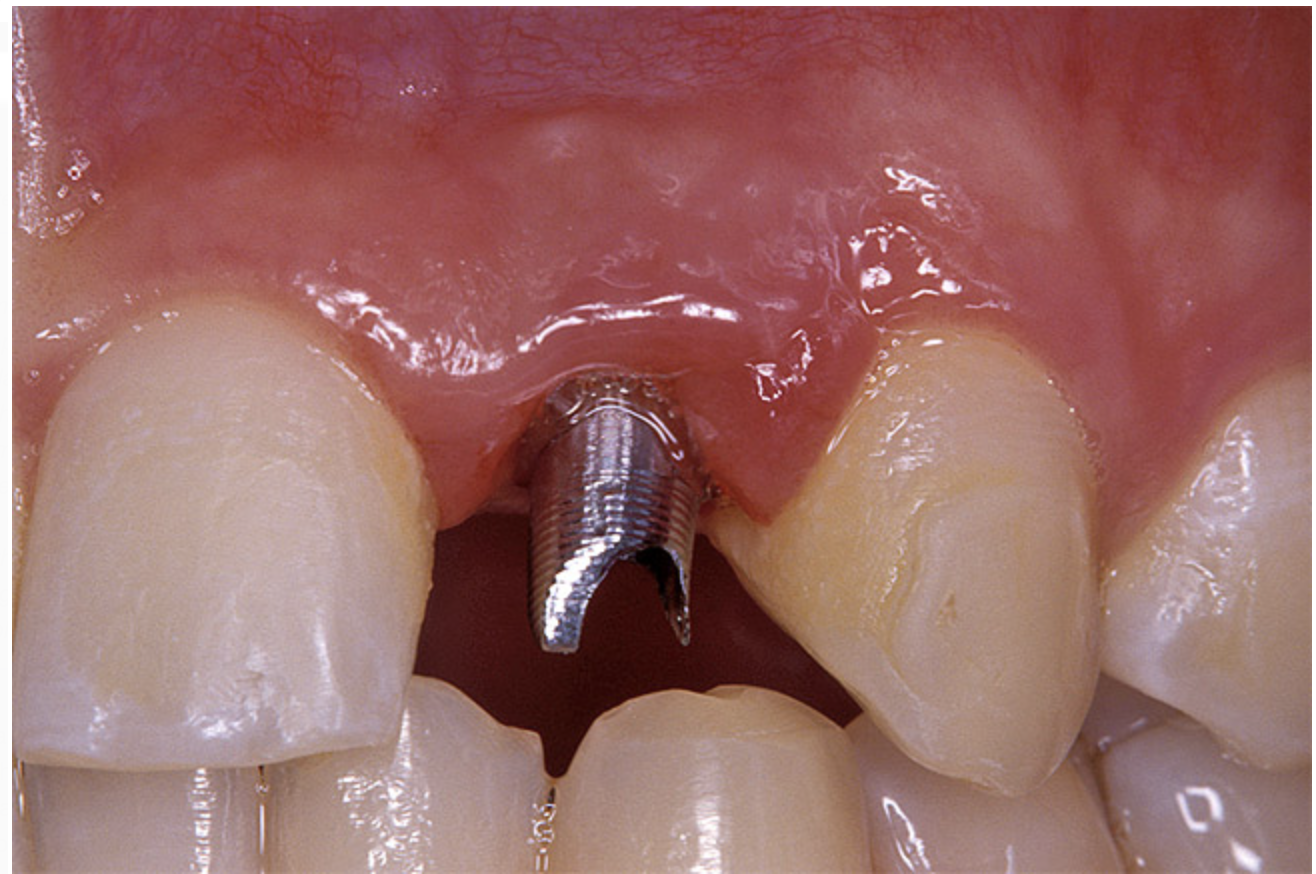

Before the day of surgery, the patient was seen by the orthodontist for the removal of the orthodontic brackets. The patient still was not pleased with the position of the two centrals, and it was determined that this would be addressed after implant placement (Figure 13A). The anatomical variations of the crestal tissue and lack of interdental papilla can be appreciated in the close-up views of the right and left sites (Figure 13B and 13C). There were no surprises on the day of surgery as all of the decisions were made during the planning phase, before the scalpel ever touched the patient. The occlusal view of the CT 3D model revealed the wider alveolar ridge on the right side and thinner crest on the left side (Figure 14A). This was confirmed when the full thickness mucoperiosteal flaps were elevated, and the underyling bone revealed (Figure 14B). The tooth-borne templates were designed to facilitate the drills and drilling sequence specific to the diameters of the predetermined implants (Figure 15A). Each template contained an embedded 5-mm long stainless steel tube, which was approximately 0.2-mm wider than each drill (just wide enough to allow for the drills to rotate freely). Once positioned over the natural teeth, the template was secure and offered precision accuracy in transferring the implant locations from the original software-designed plan, allowing the potential for internal and external irrigation (Figure 15B).

Figure 13a  Before implant surgery, the orthodontic brackets were removed, revealing (A) the position of the centrals, and (B, C) the anatomical variations of the crestal tissue and lack of interdental papilla.

Figure 13a

Figure 13b  Before implant surgery, the orthodontic brackets were removed, revealing (A) the position of the centrals, and (B, C) the anatomical variations of the crestal tissue and lack of interdental papilla.

Figure 13b

Figure 13c  Before implant surgery, the orthodontic brackets were removed, revealing (A) the position of the centrals, and (B, C) the anatomical variations of the crestal tissue and lack of interdental papilla.

Figure 13c